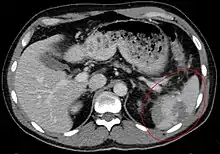

Traumatic rupture of the spleen on contrast enhanced axial CT (portal venous phase)

Splenic hematoma resulting in free abdominal blood

Splenic rupture is usually evaluated by FAST ultrasound of the abdomen.[4] Generally this is not specific to splenic injury; however, it is useful to determine the presence of free floating blood in the peritoneum.[4] A diagnostic peritoneal lavage, while not ideal, may be used to evaluate the presence of internal bleeding a person who is hemodynamically unstable.[5] The FAST exam typically serves to evaluate the need to perform a CT scan.[5] Computed tomography with IV contrast is the preferred imaging study as it can provide high quality images of the full peritoneal cavity.[4]